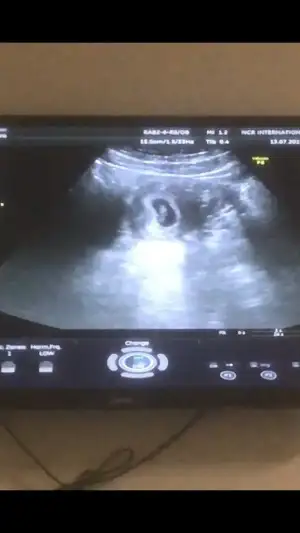

Slm kızlar Dr dan geldik keseyi gördük çok küçük henüz dedi 15 gün sora gel dedi bugün aşırı bulantı var inşallah sadece bugünlüktür iki çocuğumfada 9 ay çektim maf olmuştum hepinize bebişli günler